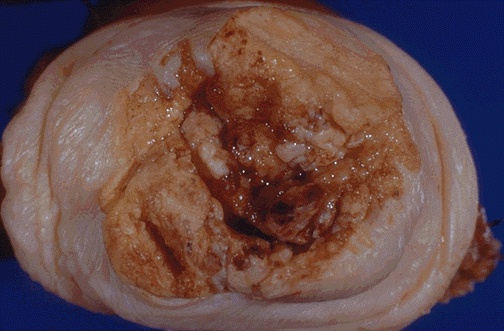

Image 1.3

The gross appearance of the cervical lesion is seen. Describe the lesion.